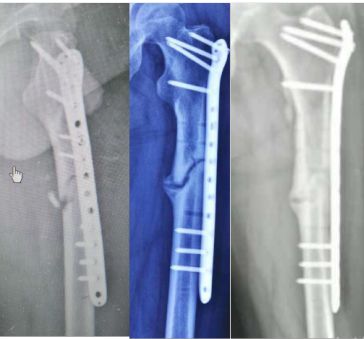

此处应用钢板有两种情况一是不会使用髓内固定,设备条件达不到;再就是理念落后见的病例少,交流少。此处外侧全部是长应力,钢板为张力钢板,内收肌力量强大,目前的钢板不能承受反复的弯曲应力,金属疲劳断裂失败率高,以下病例切开,钢丝捆绑进一步骨膜剥离,破坏了原始血肿,干扰骨愈合,都是失败原因

补救办法:剥削植骨髓内钉固定或动力髁钢板固定。

补救比较好

补救:取下一枚钉子骨折愈合了,关键是取钉子后减少了应力集中,延长了钢板的寿命,骨折愈合了。如果骨不愈合钢板迟早断裂(钢板当初放在内侧会好,蝶形骨块不会坏死,腓骨固定后外侧稳定,内外柱均衡愈合机会增加,当然最好还是髓内钉)。

取下3枚钉子骨折愈合了,与上一例同一位医生所做。张力带钢板,去除3螺钉后,钢板的应力分散,弹性增加,骨折端承受有效的应力刺激,最后骨折愈合。去除螺钉的时候如果加骨皮质剥离重新激发骨愈合会更好。(最好选髓内钉)